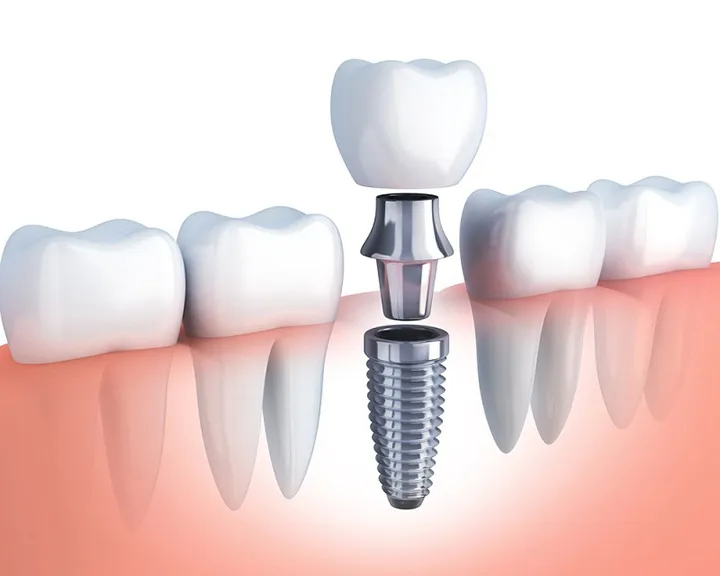

- Phẫu thuật xương: Áp dụng nếu bệnh lý tiến triển nặng gây mất xương ở mức độ nặng hơn, mất xương quá nhiều. Nha sĩ đề nghị ghép xương để bù đắp xương vào vùng mô thiếu xương, có tác dụng nâng đỡ và phát triển xương mới, làm giảm nguy cơ nhiễm trùng và mất răng.

- Ghép nướu: Bệnh nha chu khiến mô nướu tụt ra khỏi chân răng, phẫu thuật ghép nướu giúp tái tạo nướu, tạo chỗ bám cho răng. Điều này cũng giúp cải thiện thẩm mỹ cho răng với hình dáng cân đối.